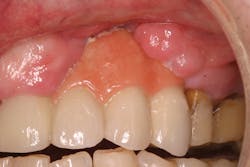

• site development to increase hard and soft tissue for pontic sites in fixed bridge prosthetics (figures 9–14);• correcting bone defects impinging upon anatomical structures after tooth extraction, such as oroantral communication (figure 18); and